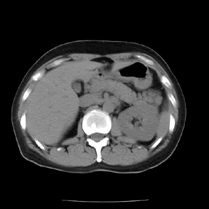

- CT検査とは、X線を人体にあてながら体内の情報を集め、コンピューターで処理をして人体の横断面(輪切り)像を撮影することです。人体の内部を見ることができることにより病気の発見に役立ちます。

- 最近のCT検査では診断に役立つ立体的な画像なども作ることができます。

胆嚢の立体画像 |

- 造影CT検査を行ったとき下のような画像も作れます(造影検査のすべてが立体画像として作成することはできません)。